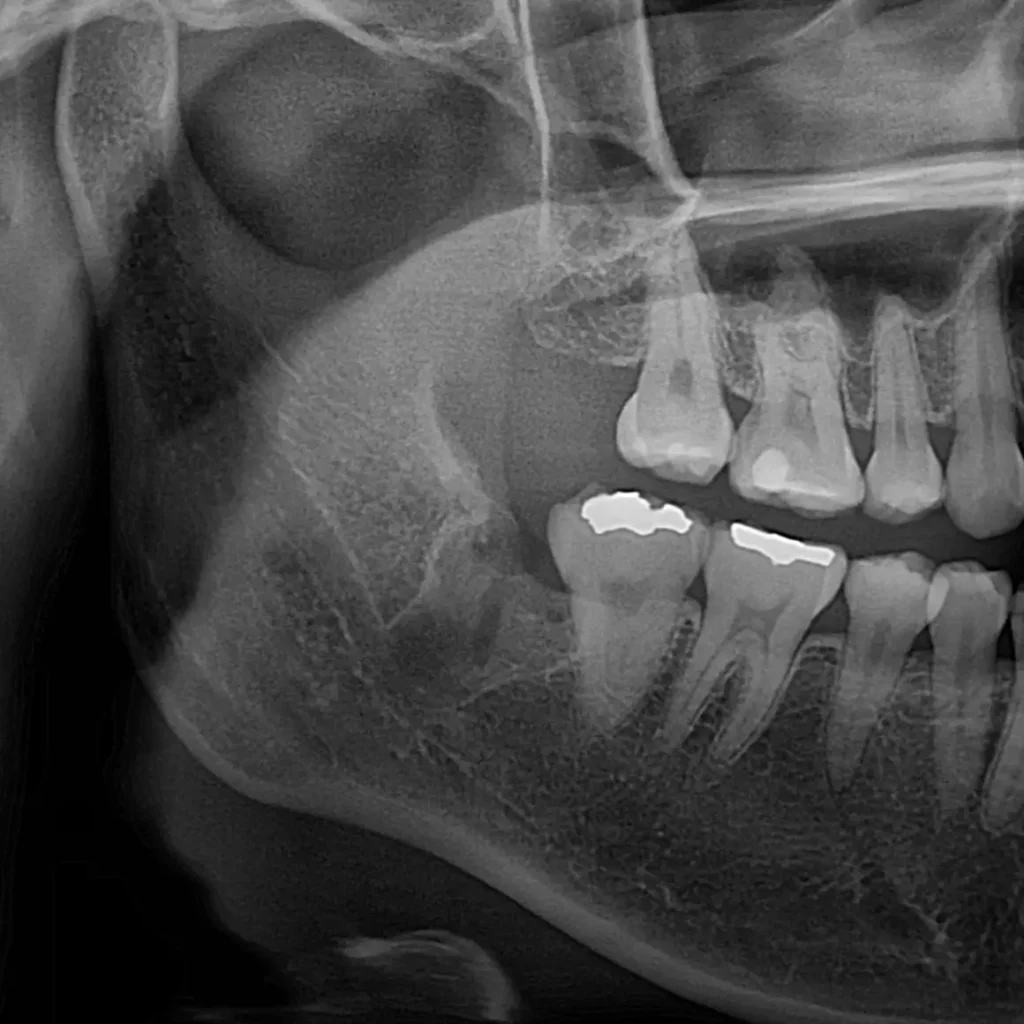

- 사랑니 발치: 왼쪽, 오른쪽 매복 사랑니를 동시에 발치했습니다.

- 충치 치료: 검진 중 발견된 왼쪽 아래 큰 어금니(#36번 치아)의 골드 인레이 하방 충치를 발견하여, 발치와 동시에 크라운 프렙(다듬기)까지 완료했습니다.